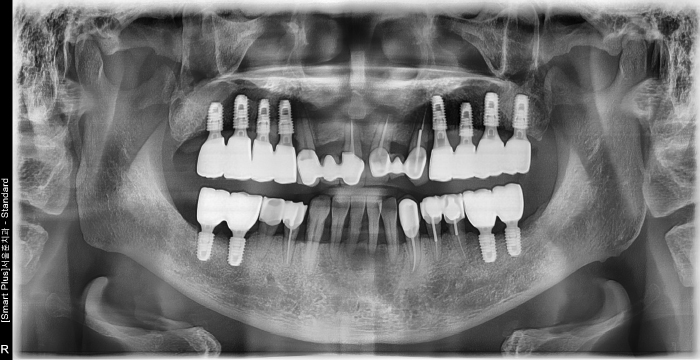

즉시 식립 임플란트 전후 사례

• 식립 전

식립 후